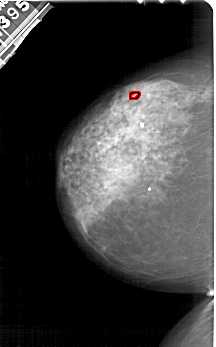

A_1544_1.RIGHT_CC

RIGHT_CC LINES 5086 PIXELS_PER_LINE 3031 BITS_PER_PIXEL 12 RESOLUTION 43.5 NON_OVERLAY